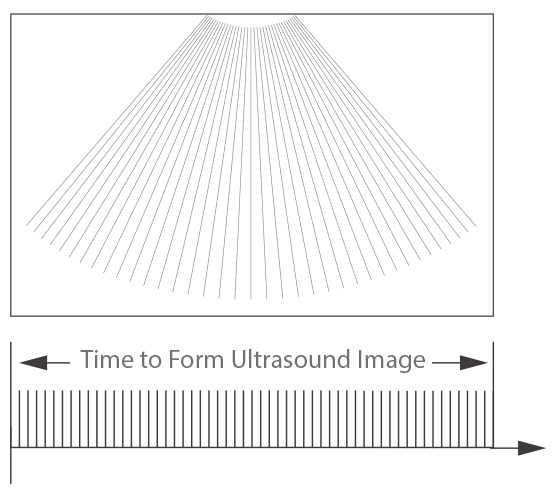

Adquisición línea por línea

Conformación de vigas tradicional

Adquisición acústica avanzada

Tecnología ZONE Sonography™+